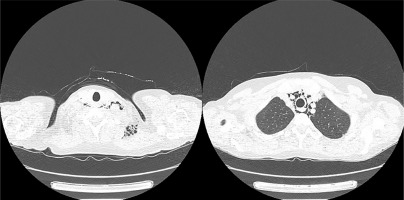

Fig. 2

Computed tomography scans with pneumomediastinum and subcutaneous emphysema detected in patient 1.

On admission she presented with slight proximal muscle weakness, subtle Gottron’s sign over the meta-carpophalangeal and proximal interphalangeal joints, palmar papules above the proximal and distal interphalangeal joints (inverse Gottron’s sign), nailfold erythema, subtle heliotrope rash, ulcerative lesions above both of the elbow joints and in the gluteal area, alopecia and isolated crackles at the bases of both lungs on auscultation. Laboratory investigations revealed hyperferritinaemia, elevated ESR and slightly increased level of AST and lactate dehydrogenase, with normal values of the remaining markers of muscle damage. Myositis-specific autoantibodies immunoblot (Euroimmun, Myositis Profile 3) revealed the strong positivity of anti-MDA5 and marked positivity of anti-Ro-52, with marginal values for anti-Jo1 and anti-PL7 antibodies. Chest CT showed interstitial lung disease with noticeable bilateral parenchymal opacities in lower lobes and “honeycombing” in the apices. Furthermore, chest CT revealed extensive yet asymptomatic pneumomediastinum and subcutaneous emphysema of the neck (Fig. 2). Bronchoscopy excluded damage to the bronchial tree, and an esophagram showed no leakage; therefore spontaneous pneumothorax was diagnosed. Computed tomography of the abdomen and pelvis showed no signs of malignancy. Echocardiographic examination revealed worsening of left and right ventricular systolic function (LVEF = 52%), compared to the examination performed a year earlier. Treatment with mycophenolate mofetil (2 g/day) was initiated and methylprednisolone (12 mg/day) was continued. Weight stabilized, but after two months of treatment myalgia and exacerbation of ulcerative skin lesions were observed. The patient was administered cyclophosphamide (CTX, 1,000 mg/month, 3 cycles), methylprednisolone (12 mg/day) and sildenafil (20 mg/day). Despite an initial modest improvement in the extent of the ulcerations, in the following months the disease progressed. Due to frequent infections of ulcerative lesions, the patient underwent topical antibiotic therapies. Cyclophosphamide was changed to cyclosporine (150 mg/day) with increased doses of methylprednisolone (16 mg/day) and sildenafil (25 mg/day). Skin ulcerations started to heal, and new lesions did not appear. Unfortunately, the ulcers continued to become infected, and special dressings and targeted antibiotic therapy were needed under supervision of a surgeon. After 6 months, disease remission was achieved. Due to the involvement of more than 20% of the lung parenchyma, nintedanib (150 mg twice a day) was added.